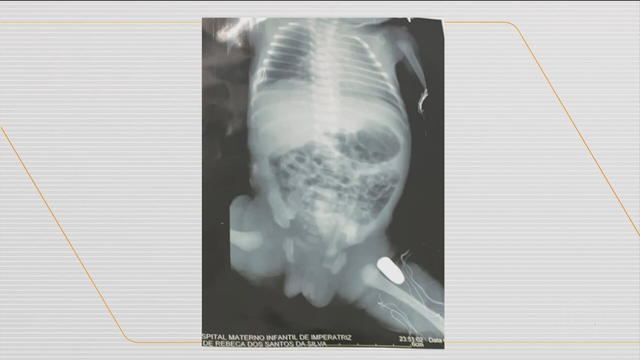

Uma bebê de 32 semanas de gestação, que foi atingida por um tiro dentro da barriga da mãe, uma adolescente de 15 anos, na cidade de Imperatriz, foi submetida a uma cirurgia para remoção do projétil da perna esquerda.

Os tiros atingiram a barriga da adolescente, que foi socorrida e levada para a Maternidade de Alto Risco de Imperatriz, onde passou por uma cesárea de emergência. Exames de imagem mostraram que um dos tiros atingiu a perna esquerda do bebê.